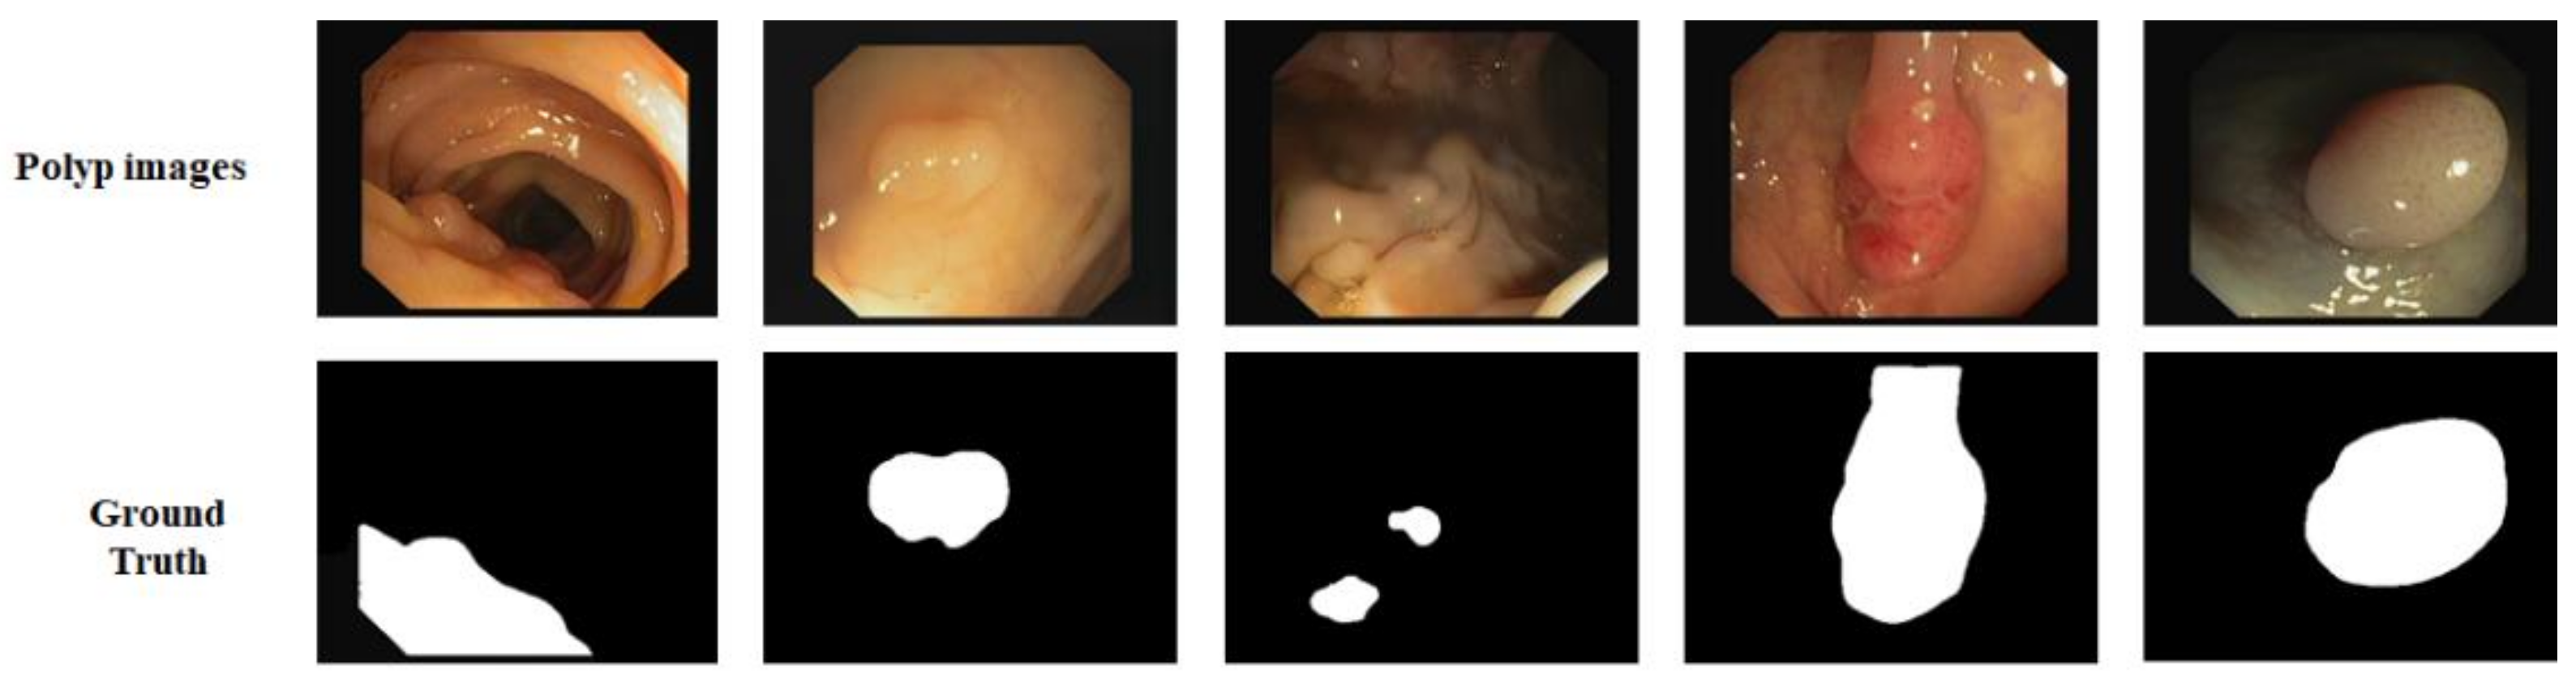

CVC-612: In addition, we used the CVC-612 [49] dataset, this database built in collaboration with the Hospital Clinic of Barcelona, Spain. CVC-612 has been generated from 23 different video studies from standard colonoscopy interventions with white light. CVC-612 database comprises 612 polyp images of size 576 × 768 pixels from 31 colonoscopy series. The images were split into training, validation, and testing sets in the ratio of 80:10:10. All training, validation, and testing were performed with an image size of 224 × 224 pixels. Figure 6 shows some example images and corresponding masks from the CVC-612 dataset.

Figure 6.

Images and ground truth masks from the CVC-612 dataset.